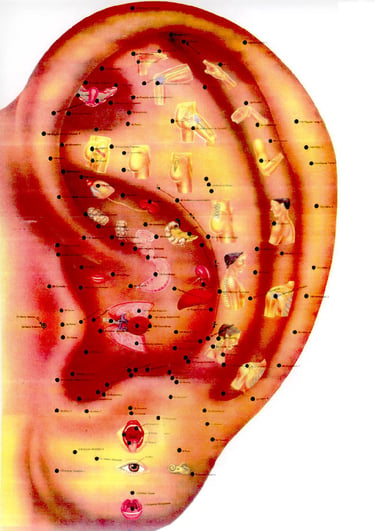

Libros de acupuntura y MTC

Galería

Momentos capturados de la medicina tradicional china en acción